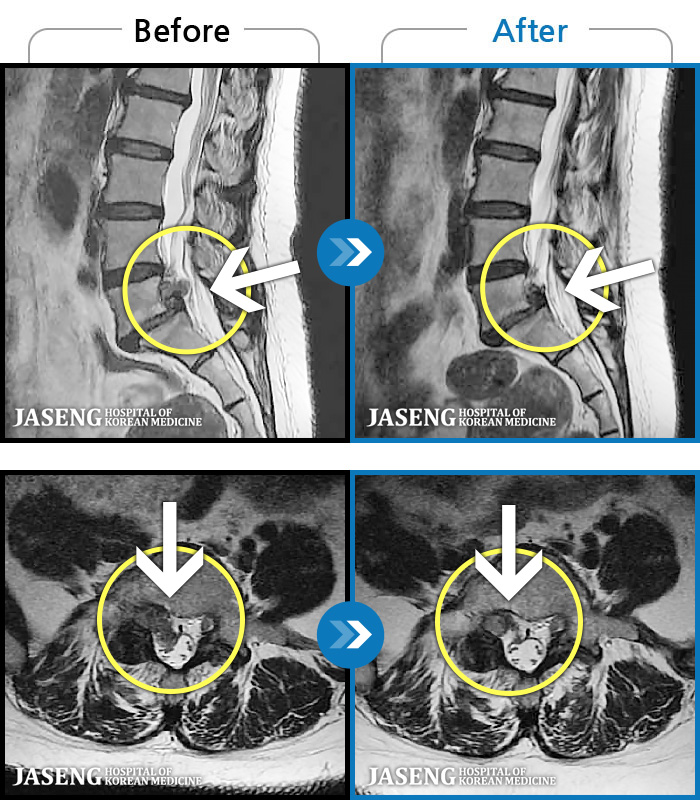

- MRI ġ

MRI ġ

㸮 ϻ .

ǿ

Ȼ

ȯ

㸮ũ